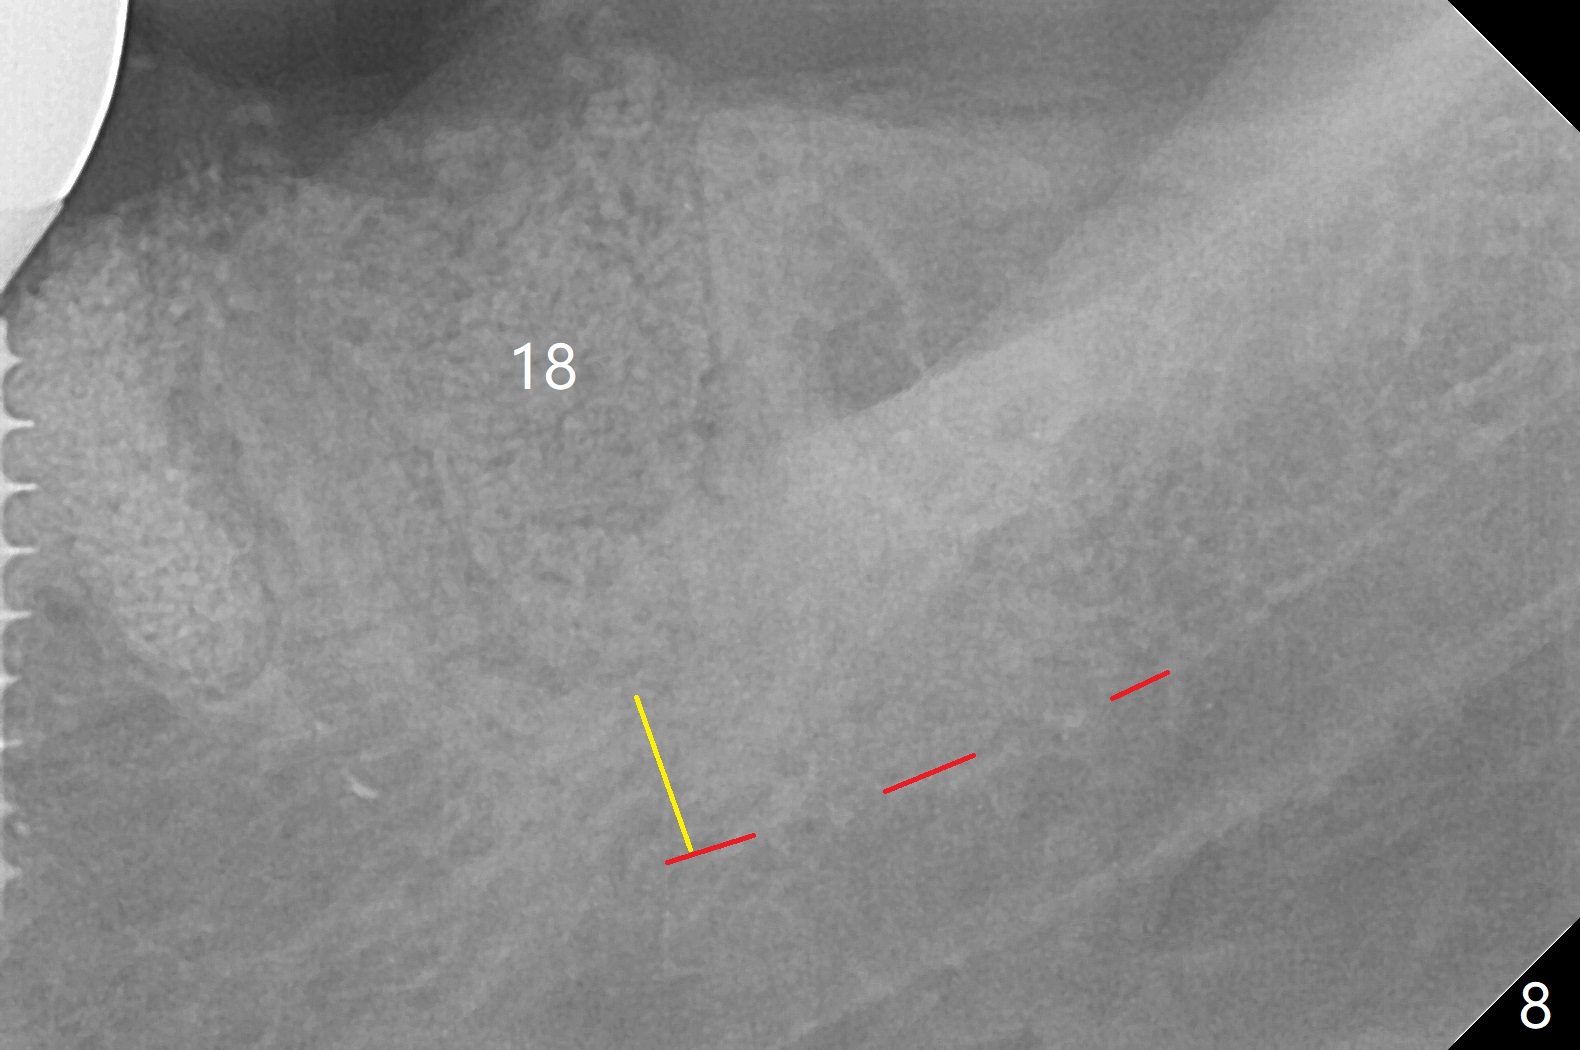

After making a 10 mm incision at the site of #19, #15c blade is used as an osteotome to start bone expansion, followed by Magic Split and Magic Expander (ME, 3 mm in diameter). The depth is approximately the bottom of the mesial socket. The osteotomy beyond the socket has to be done with 1.6 mm pilot drill (Fig.1) in combination of ME. Following ME 4.3 mm and Magic Drill (MD) 3.8 mm for 15 mm (gingival level), a 4.5x11 mm dummy implant is placed with 50 Ncm (Fig.3); the implant looks narrow for the edentulous space. After ME 4.8, MD 4.3 for 13 mm and Final Drill for 15 mm, a 5x11 mm IBS is inserted with >50 Ncm (Fig.3). With 2 more turns of the implant, a 6.5x4(2) mm abutment is placed (Fig.4). Periodontal dressing is applied around the abutment for additional retention. A provisional is fabricated 3 weeks postop. The provisional and abutment are loose 4 months postop (Fig.5). After retightening the abutment, impression is taken for final restoration. There is no bone loss 1 year 3 months post cementation (Fig.6). After use of #100 file (Fig.7), the canal is debrided with #140 file with 1.5 mm shorter in working length with placement of Calcium Hydroxide paste. Pain gets worse post RCT retreatment. There is limited native bone for primary stability when an immediate implant is placed (red dashed line: the superior border of the Inferior Alveolar Canal). Prepare IS regular and extra wide kits and tissue-level implants (>5 mm). Socket preservation may be done instead. If the socket is large and the vein is not so small, prepare PRF. In fact blood drawing fails. When the tooth is extracted, it is sensitive to remove granulation tissue. Socket preservation is done with Vanilla graft at #18 (Fig.8); there is ~3.5 mm bone between the bottom of the single socket and the Inferior Alveolar Canal (red dashed line). The socket at #18 seems to have healed 4 months post extraction (Fig.19), but the bone height appears to have been reduced (compare Fig.10,11). The buccolingual width is also decreased (Fig.12,13). A 4.5 or 5.0x10 mm implant is appropriate for the site (Fig.14). There is no bone loss at #19 (which may be associated with the bone expansion) 1.5 years post cementation (Fig.15). Therefore the osteotomy at #18 will be assisted with bone expanders after 2.2 mm drill.